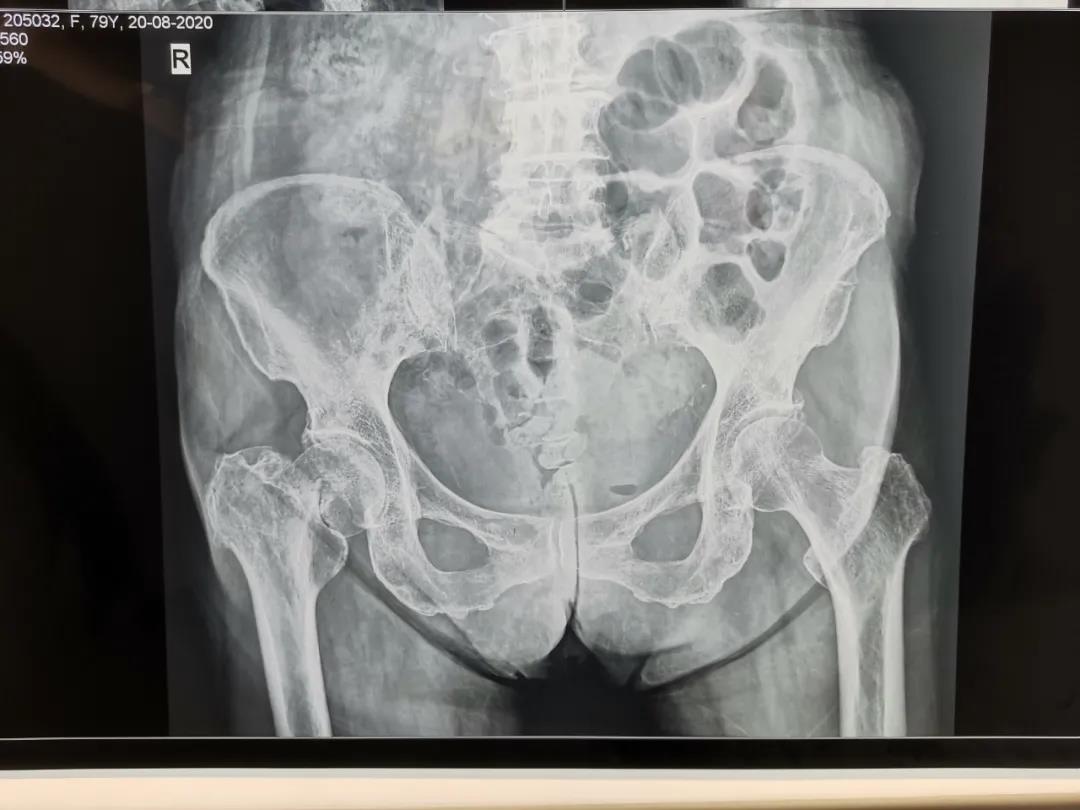

人工股骨頭置換手術(shù)治療老年股骨頸骨折

股骨頸骨折是老年骨質(zhì)疏松性骨折最常見(jiàn)的一種髖部骨折,是老年患者致殘和致死的主要原因之一,發(fā)生髖部骨折后1年內(nèi),20%的患者會(huì)死于各種并發(fā)癥,約50%的患者致殘,生活質(zhì)量明顯下降。骨折后病人往往因肢體疼痛、不能行走致長(zhǎng)期臥床,部分骨折的病人還伴有全身基礎(chǔ)疾病,如果病人能夠盡早下地活動(dòng),減少臥床時(shí)間,就能有效減少臥床并發(fā)癥發(fā)生。為達(dá)到這個(gè)目的,越來(lái)越多的病人選擇了手術(shù)治療。對(duì)于老年人的股骨頸骨折而言,較好的手術(shù)方式是人工髖關(guān)節(jié)置換術(shù)。

79歲的杜大娘在家不慎摔倒,跌傷右髖部,許冬雷主任為其主刀行右股骨頸骨折人工股骨頭置換術(shù),用時(shí)短,出血少,患者清醒后就說(shuō)腿不疼了,術(shù)后第一天見(jiàn)到醫(yī)生就豎大拇指,激動(dòng)地說(shuō):“手術(shù)前我很害怕、也很焦慮,沒(méi)想到手術(shù)后一點(diǎn)也沒(méi)有感覺(jué)到疼痛”。術(shù)后第3天就可以下地活動(dòng)了,老人的生活又恢復(fù)了往日的悠然自在。